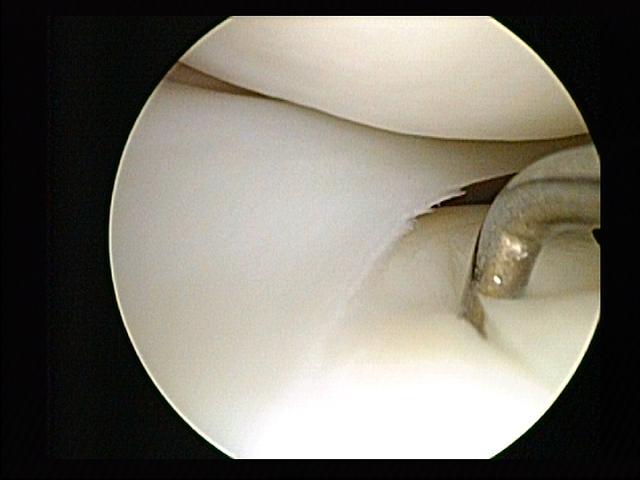

. Can you describe the radiographs? These are AP and lateral radiographs of the left tibia and fibula showing…